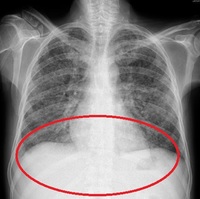

- ¾ËÄÚ¿Ã Áßµ¶À̾ú´ø 40´ë ³²¼ºÀÌ ±â»ýÃæ °¨¿° ÈÄ »ç¸ÁÇÑ »ç·Ê°¡ º¸°íµÆ´Ù.¸ß½ÃÄÚ ´©¿¡º¸·¹¿Â ÀÚÄ¡´ë ºÎ¼Ó º´¿ø ÀÓ»ó±â»ýÃæÇаú ÀÇ·áÁø¿¡ µû¸£¸é, 40¼¼ ³²¼ºÀÌ 2ÁÖ°£ º¹Åë°ú ±¸Åä Áõ»óÀÌ ³ªÅ¸³ª ³»¿øÇß´Ù. üÁßµµ 10kg..